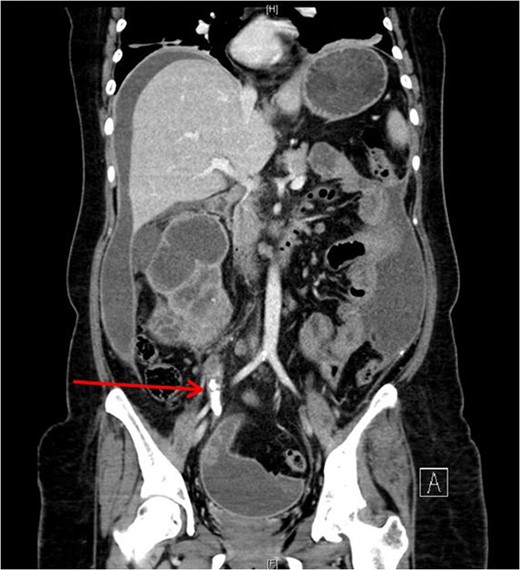

Xanthogranulomatous pyelonephritis (XGPN) is a rare form of chronic pyelonephritis with progressive loss of renal function. Commonly, obstructing urinary calculi are seen. It is difficult to differentiate between XGPN and malignancy in many cases, and the diagnosis is usually only confirmed post-operatively upon histopathological examination of the specimen. Surgical treatment is often the main treatment modality due to suspicion for malignancy. Here, we present a case of XGPN that presented with abdominal distension, which was eventually discovered to be due to a preperitoneal abscess.

She underwent insertion of a right percutaneous nephrostomy drain, percutaneous drainage of the anterior abdominal collection, as well as a percutaneous biopsy of the right renal soft tissue lesion. Urine cultures from the percutaneous nephrostomy grew Proteus mirabilis. Fluid cytology from the abdominal collection showed acute inflammatory cells. Biopsy of the renal lesion showed xanthogranulomatous inflammation.

After a period of antibiotic treatment, she underwent open right nephroureterectomy with exploration, drainage and washout of the preperitoneal collection. During surgery, 1 l of pus was drained from the preperitoneal space, and cultures grew P. mirabilis. The ureter was ligated below the level of the calculus and removed together with the kidney. Final histopathology results showed XGPN with no evidence of malignancy in the kidney or peritoneal lining.

Our patient had an atypical presentation with abdominal distension and presumed ascites, which was eventually revealed to be an anterior preperitoneal collection secondary to infection. Although the initial suspicion was that of a malignant process complicated by ascites, subsequent cytology and histopathological results showed that it was likely benign. In view of the non-functioning renal unit and significant abdominal collection, she underwent definitive surgery.

The most common urinary pathogen identified was Escherichiacoli [3], and common areas of involvement were the retroperitoneum and psoas muscle. In our patient, the retroperitoneal space was surprisingly not greatly involved, but rather it was the anterior preperitoneal space that had significant adhesions and inflammation. The pathogen identified from both nephrostomy and preperitoneal collection was P. mirabilis, showing that both pathologies were linked.